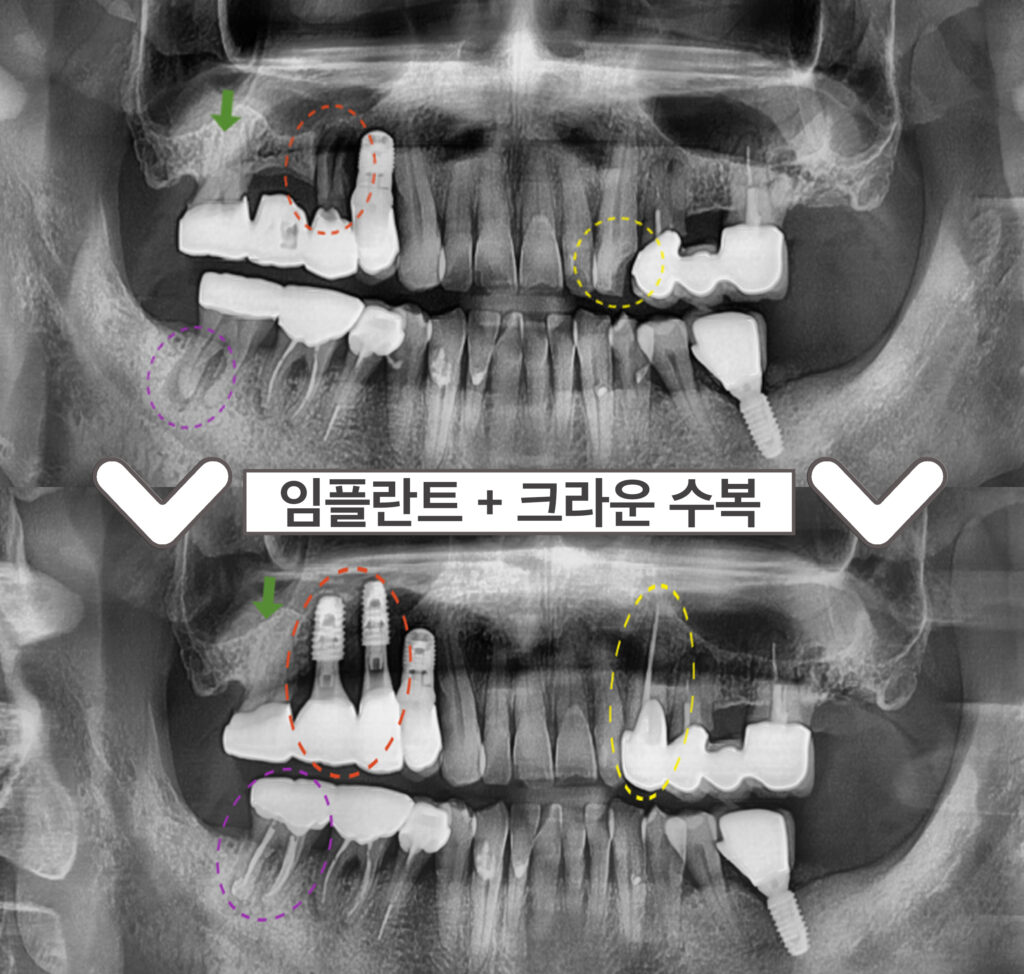

처음 내원 당시

환.자분의 파노라마 사진을 살펴보면

노란색 동그라미 표시의

위턱 왼쪽 송곳니(#23)이

충치로 인해 치아머리가 파절 되어 있어

신경치료 후 크라운 수복이 필요하였으며,

빨간색 동그라미 표시의

위턱 오른쪽 작은 어금니(#15)는

치아 뿌리가 파절되어 있어 발치 후

기존 상실된 첫 번째 큰 어금니(#16)와 함께

상악동 거상술을 동반하여

임플란트 식립이 필요하였습니다.

초록색 화살표의

위턱 오른쪽 두 번째 큰 어금니(#17)는

브릿지 제거 후 상태 평가 후

다시 크라운 수복 계획을

진행하기로 하였으며,

보라색 동그라미 표시의

아래턱 오른쪽 두 번째 큰 어금니(#47)는

타진 검사와 씹.는 검사에서

증.상이 있으며,

치아 뿌리 끝으로 병소가 관찰되어

신경치.료 후 크라운 치료가 필요했는데요.

임플란트 / 크라운 수복

신경치료 후 크라운 수복을

모두 마무리 한 모습입니다.